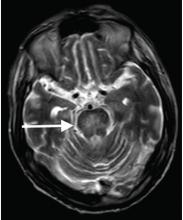

Although CT may underestimate osmotic demyelination syndrome, the typical radiologic findings on brain MRI are hyperintense lesions in the central pons or associated extrapontine structures on T2-weighted and fluid-attenuated inversion recovery sequences.4

Our patient’s clinical course and high hemoglobin A1c suggested prolonged hyperglycemia and high serum osmolality before his admission. After his admission, aggressive hydration and insulin therapy corrected the hyperglycemia and serum osmolality too rapidly for his brain cells to adjust to the change. It was reasonable to suspect a hyperosmolar hyperglycemic state as one of the main causes of his mental status change and ataxia. This, along with lack of improvement in his impaired metal status and new-onset ataxia despite treatment, led to suspicion of osmotic demyelination syndrome. His diminished bilateral knee-jerk and ankle-jerk responses more likely represented diabetic neuropathy rather than osmotic demyelination syndrome.